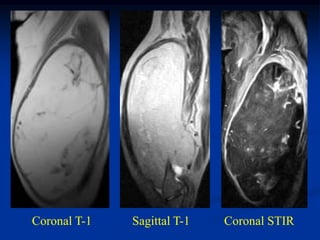

Coronal T-1   Sagittal T-1   Coronal STIR

Case #270.1 Intramuscular lipoma Axial T-1 T-1 STIR 72 year female with painless mass in anterior thigh for years